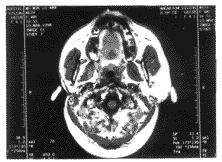

先天性单侧腮腺缺失1例

先天性一侧腮腺发育缺失文献上见有报道 ......